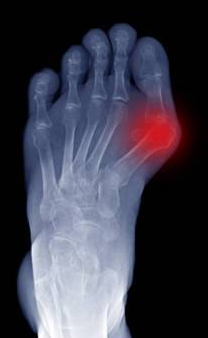

Deformidade progressiva do antepé com impacto funcional e mecânico.

Confirmamos deformidade e impacto funcional. Planeamento baseado em critérios clínicos e imagem quando indicada. Opções: conservador, controlo de carga e, em casos selecionados, cirurgia (incl. minimamente invasiva).